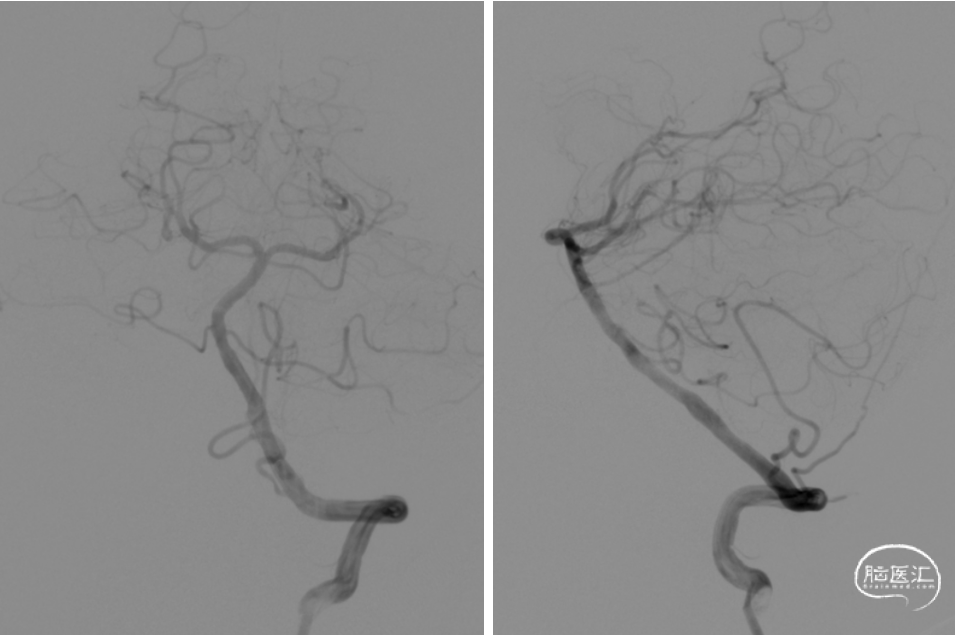

撤出球囊,将APOLLO3.0*13mm支架沿微导丝送至基底动脉狭窄处,定位准确后以10atm压力释放,复查造影基底动脉显影良好,狭窄处明显改善,无明显残余狭窄,双侧大脑后动脉、双侧小脑上动脉显影良好。

撤出撤出支架输送系统及微导丝,行平板CT未见出血及造影剂渗出。撤出8FGUiding。术毕。

将APOLLO3.0*13mm支架沿微导丝送至基底动脉狭窄处,定位准确后以10atm压力释放,复查造影。